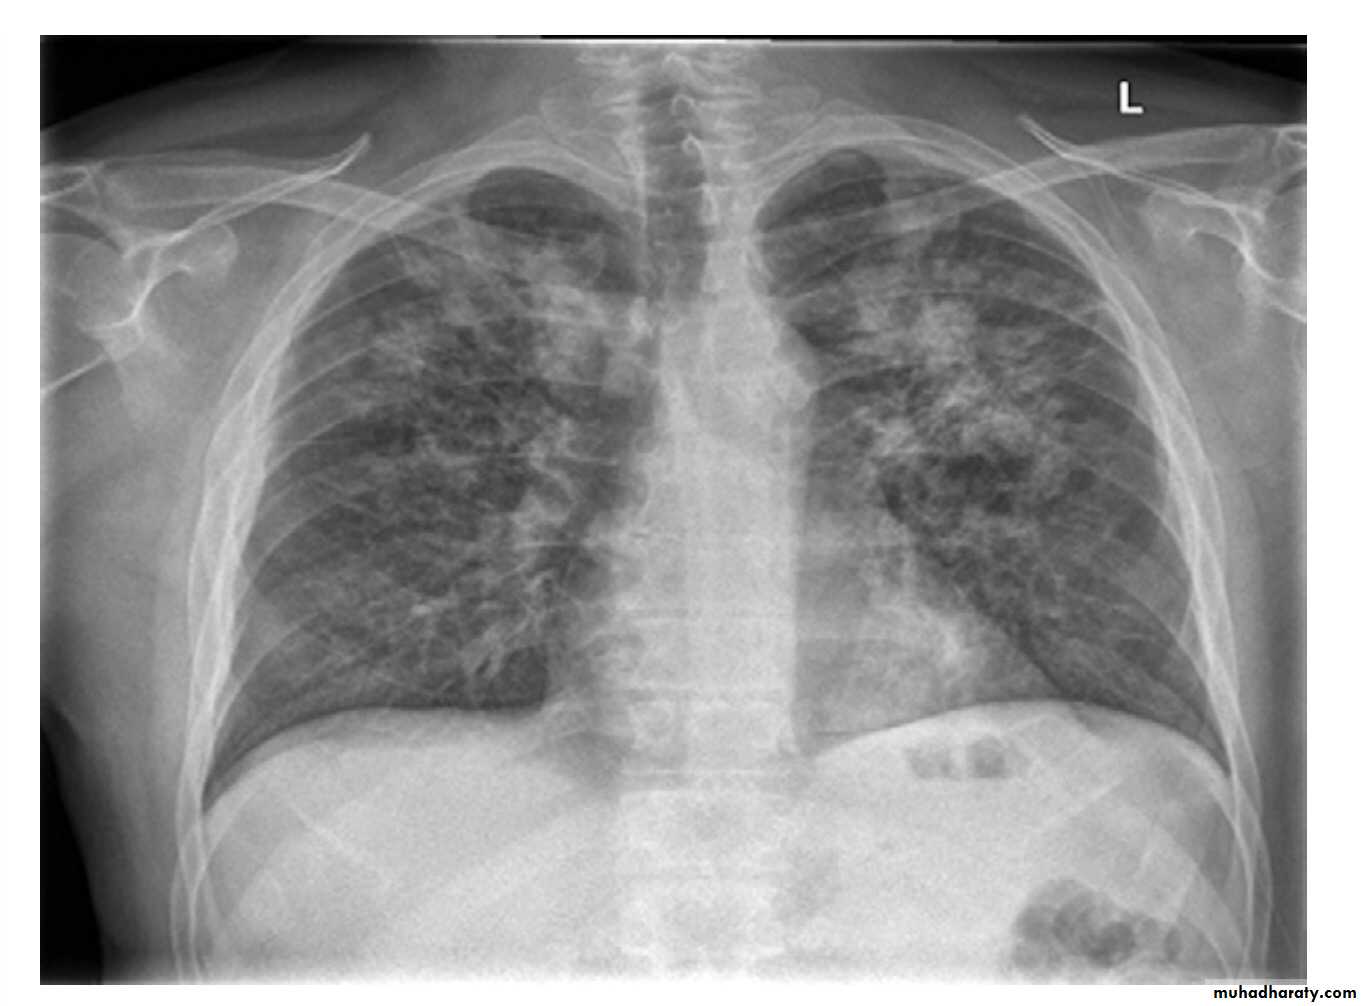

The presence of unexplained cough for more than 2–3 weeks or typical chest X-ray changes should prompt further investigation.Direct microscopy of sputum remains the most important first step (typically positive when 5000–10000 organisms are present).

A diagnosis of smear-negative TB may be made in advance of culture if the chest X-ray appearances are typical of TB and there is no response to a broad-spectrum antibiotic

Typical changes of tuberculosis. The chest X-ray shows bilateral upper lobe airspace shadowing with cavitation.